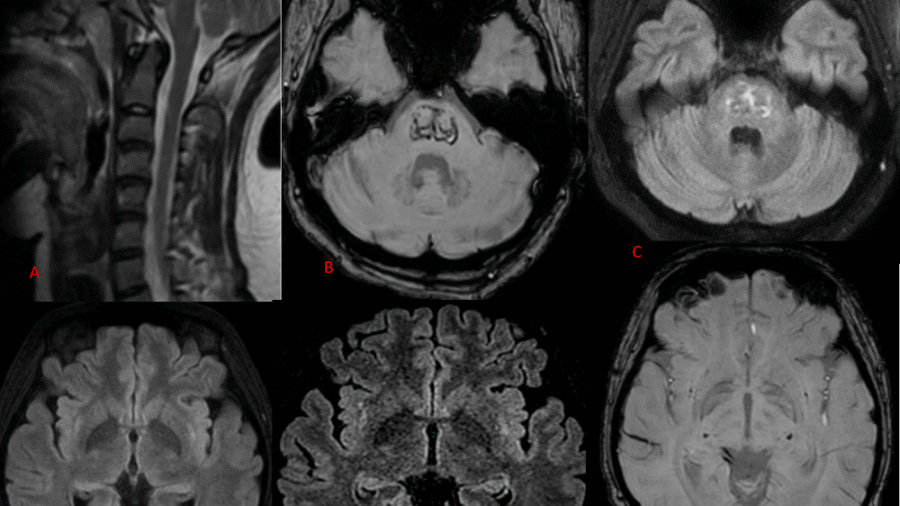

A rare case of osmotic pontine demyelination due to hypokalemia in a patient with Sjogren syndrome and renal tubular acidosis.

A 36 year old hypertensive male presented with gradually progressive weakness of bilateral upper and lower limb weakness since 1-2 months.